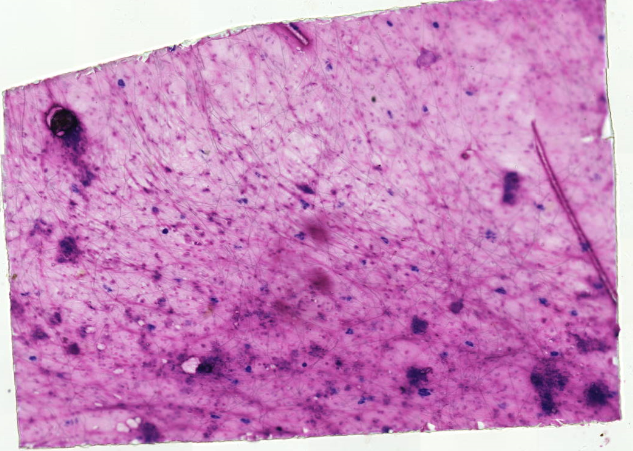

Рыхлая волокнистая соединительная ткань

Loose areolar connective tissue